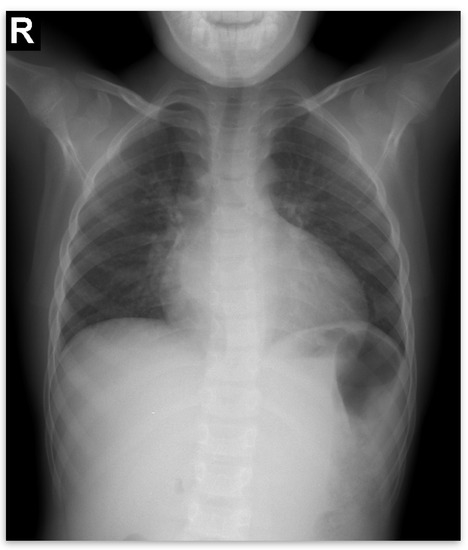

Due to the poor medical condition, with advanced renal failure, acidosis, arterial hypertension, the patient required the urgent initiation of hemodialysis. At the same time, we continued investigations for the etiology of renal failure (Table 1). We excluded the reflux nephropathy (secondary to primary or secondary vesicoureteral reflux, or posterior urethral valve) by voiding cystourethrogram (Figure 1).

Voiding mictional cystourethrogram (Figure 1)

excluded the presence of a posterior urethral valve or primary vesicoureteral reflux

Figure 1. Voiding mictional cystourethrogram.